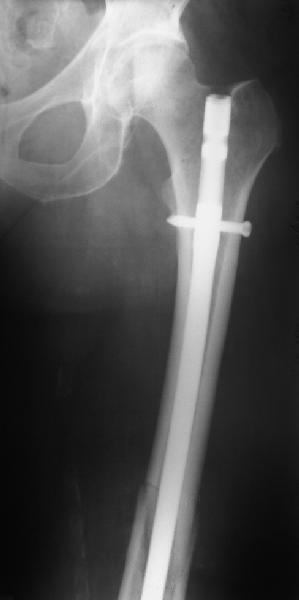

В приложении - недавний перипротезный перелом.